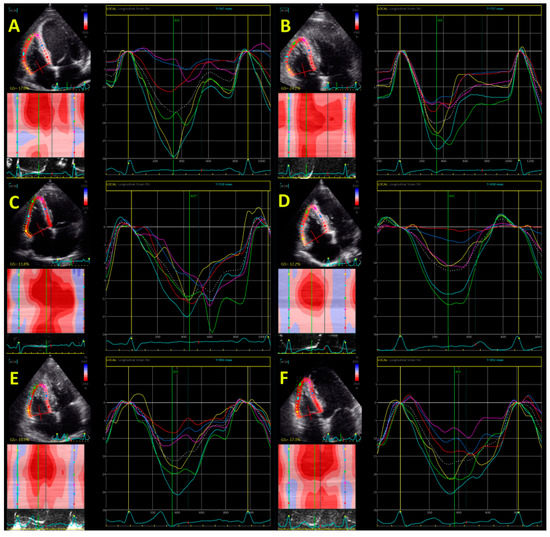

- D’Andrea, A.; Limongelli, G.; Baldini, L.; Verrengia, M.; Carbone, A.; Di Palma, E.; Vastarella, R.; Masarone, D.; Tagliamonte, G.; Riegler, L.; et al. Exercise speckle-tracking strain imaging demonstrates impaired right ventricular contractile reserve in hypertrophic cardiomyopathy. Int. J. Cardiol. 2017, 227, 209–216. [Google Scholar] [CrossRef] [PubMed]